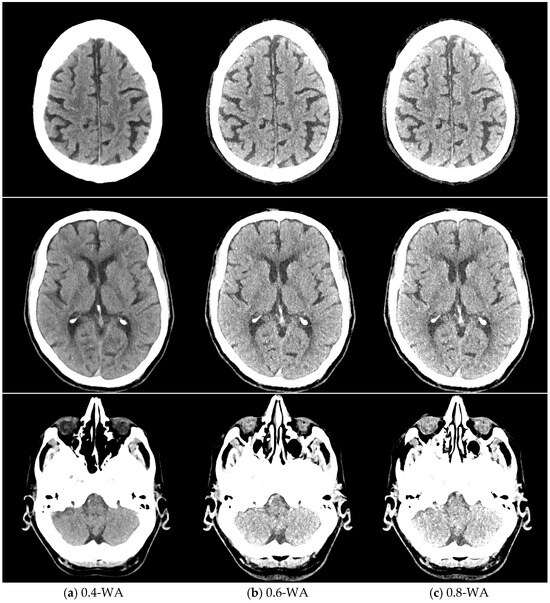

Figure 2.

Weighted average (WA) image datasets with different weighting factors (0 to 1) on an anthropomorphic phantom at the level of basal ganglia with the scout image. All images are displayed using the same window width and window level (WW 80, WL 35).

The qualitative assessment of the image quality of the 0.4-WA, 0.6-WA, and 0.8-WA patient reconstructions (Figure 5) was performed according to the methodology described in Section 2.1.3. of the phantom study.

Figure 5.

Weighted average (WA) image datasets of the brain with different weighting factors—0.4 (a), 0.6 (b), and 0.8 (c) of the same patient at the level of the frontoparietal lobe, basal ganglia, and posterior fossa. All images are displayed with the same window width and level (WW 80, WL 35).

GM–WM CNR and noise generally increased when WF values increased from 0 to 1 (Figure 6). The 0.9-WA reconstructions had the highest CNR, and 0-WA and 0.1-WA had the lowest. SCA and PFAI were lowest for 0-WA images and highest for 1-WA images. Qualitative analysis showed unacceptable GM–WM contrast on 0-WA, 0.1-WA, and 0.2-WA image datasets for two readers. All readers rated GM–WM contrast as very good or excellent at 0.5-WA, 0.6-WA, and 0.7-WA. No or minimal posterior fossa and subcalvarial artifacts were noted at 0-WA, 0.1-WA, 0.2-WA, 0.3-WA, and 0.4-WA, while 0.9-WA and 1-WA reconstructions were considered unacceptable or for very limited evaluation by all readers. The overall IQ was rated as very good or excellent by at least two readers for the 0.5-WA, 0.6-WA, 0.7-WA, and 0.8-WA image datasets. The interrater consistency results for the assessment of the different IQ metrics for all 11 image datasets are presented in Table 2. The agreement for SCA assessment was moderate, while the interrater agreement for noise, GM–WM contrast, PFA, and overall IQ was good.

Based on the results of both quantitative and qualitative phantom analyses, WA reconstructions with WFs of 0.4, 0.6, and 0.8 were selected for the patient study. The inclusion of WF 0.4 was essential as it is routinely used in clinical practice; thus, it provides a standard for comparison. The quantitative analysis showed that the difference in GM–WM CNR between WFs 0.4 and 0.5 was smaller than between 0.5 and 0.6, and the difference between WFs 0.7 and 0.8 was also minimal. In addition, WFs lower than 0.4 and higher than 0.8 were classified as unacceptable or suitable for very limited evaluation based on the analyses and were therefore excluded from further study.